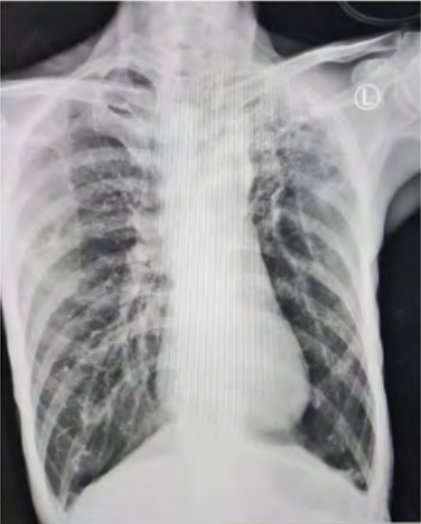

Satu jam setelah dilakukan dekompresi jarum, pasien merasakan sesak napasnya berkurang, pasien mulai merasa nyaman duduk bersandar dan retraksi berkurang. Pada pemeriksaan auskultasi, suara napas sisi paru-paru kanan mulai terdengar, meskipun masih lebih lemah dibanding suara napas di sisi paru-paru kiri. Tanda-tanda vital setelah dilakukan dekompresi jarum sebagai berikut: tekanan darah 108/75 mmHg, frekuensi nadi 110 kali per menit, frekuensi napas 30 kali per menit, dan saturasi oksigen 95-96% dengan oksigen non- rebreather mask 10 liter per menit. Hasil pemeriksaan radiologi foto polos toraks setelah dekompresi jarum adalah tampak penurunan volume pneumothorax pada hemitoraks sisi kanan, dengan ukuran sekitar 15%, dari sebelumnya 28%. Tampak pengurangan densitas bercak infiltrat pada lapangan paru-paru sisi kanan. Bercak infiltrat pada lapangan paru-paru sisi kiri tidak tampak perubahan. Efusi pleura bilateral relatif status quo ad anthem. Tidak tampak kelainan pada cor saat dilakukan pemeriksaan.

Gambar 2. Foto polos toraks setelah dekompresi jarum. Gambaran pneumothorax di sisi kanan telah berkurang dibanding sebelumnya.